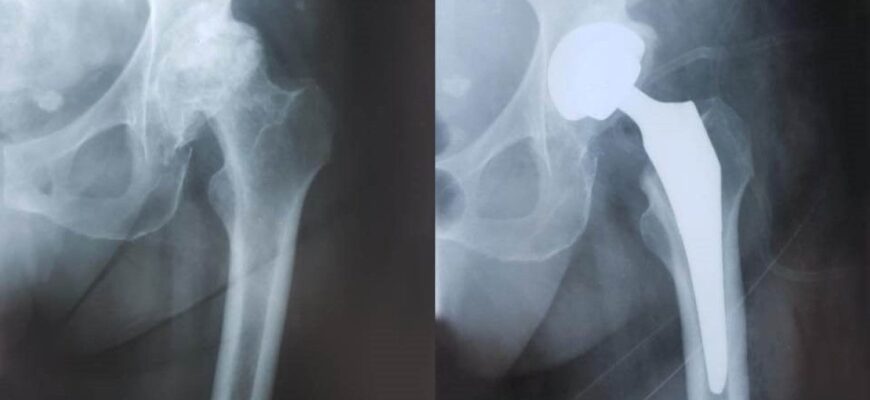

Життя після заміни кульшового суглоба: відновлення та поради лікарів

Життя після операції по заміні суглоба кульшового: нова реальність